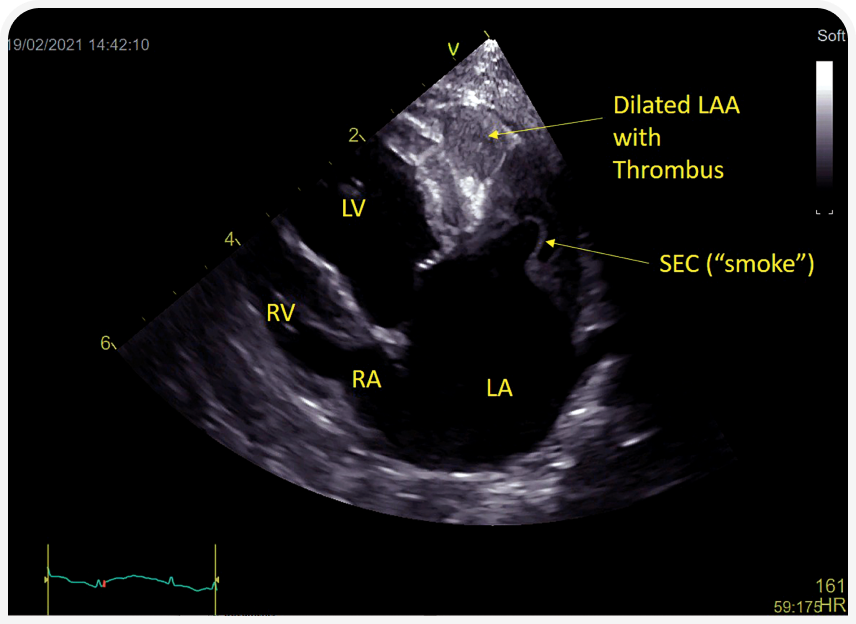

К ним относятся наличие спонтанного эхо-контраста («дым») (Рисунок 7), увеличение левого предсердия от умеренной до тяжелой степени, снижение скорости движения по ушку левого предсердия, уменьшение фракционного укорочения предсердий, уменьшение фракции выброса из левого предсердия и увеличение толщины стенки левого желудочка; все эти признаки у кошек считают показаниями для начала терапии клопидогрелом при бессимптомном течении заболевания.